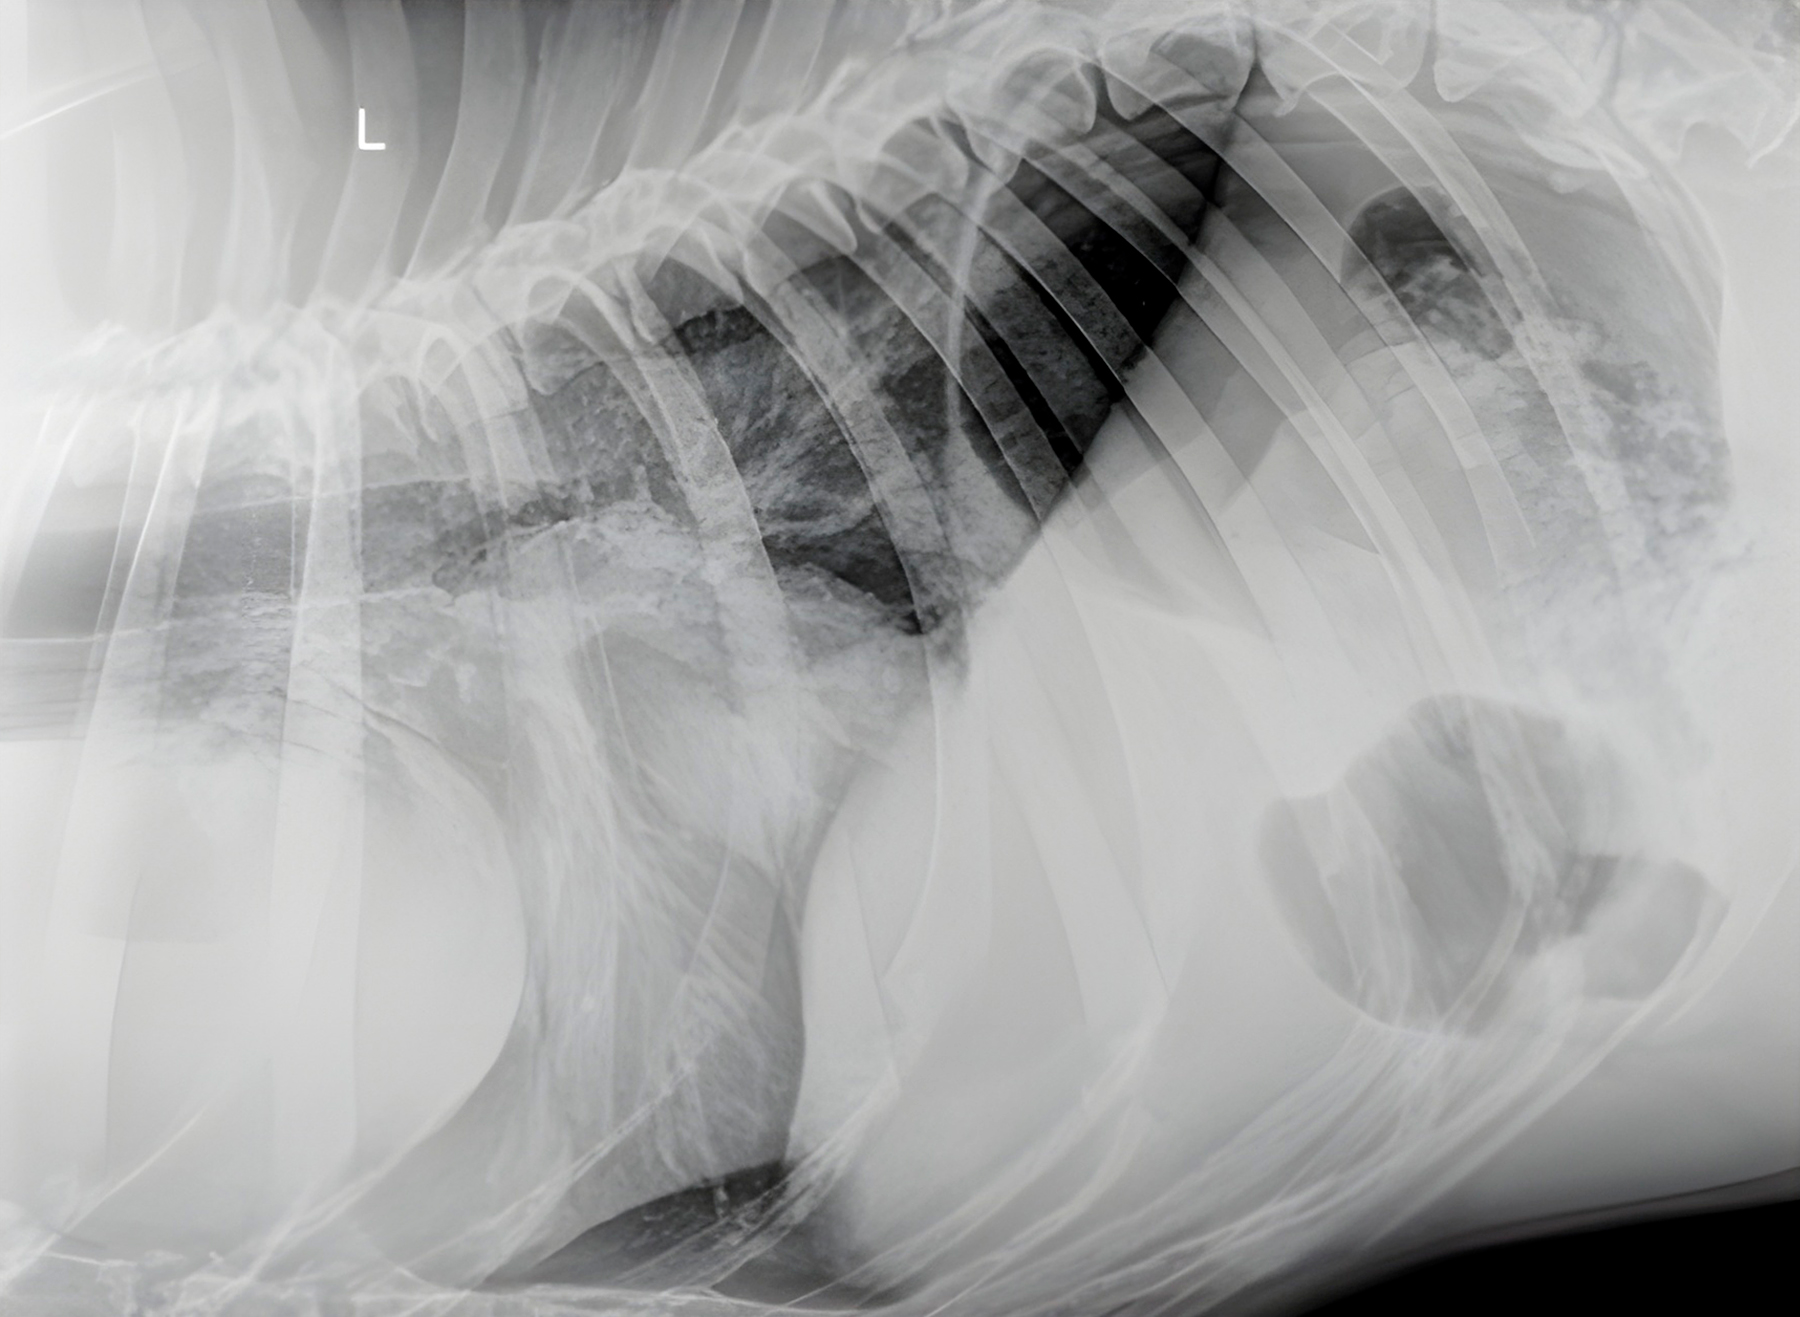

Paciente: Canino, raza Boxer, 11 años de edad.

Motivo de Consulta: Pérdida de peso severa y compromiso respiratorio.

Hallazgos Preliminares: La evaluación radiográfica torácica evidenció una estructura de densidad de partes blandas adyacente a la silueta cardíaca.